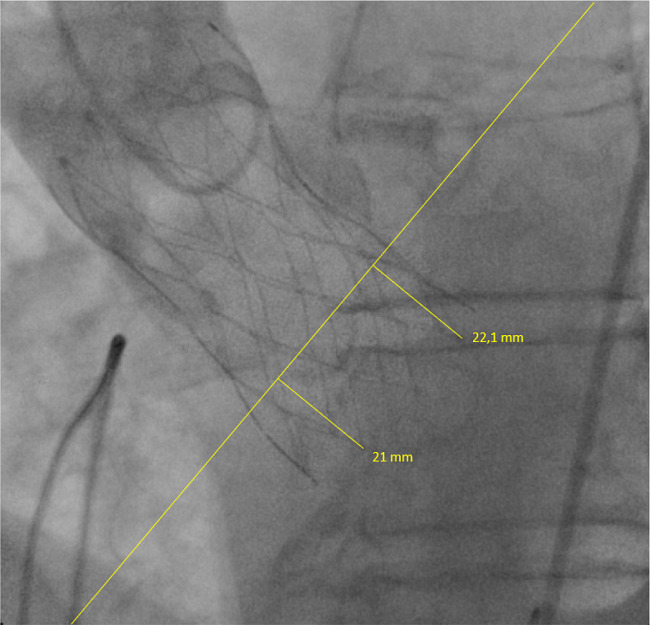

A 75-year-old male patient with severe aortic stenosis and severe renal failure was admitted to our hospital for a TAVI procedure. He successfully underwent implantation of a 29-mm Medtronic CoreValve Evolut R self-expandable aortic prosthesis via transfemoral access through the device implanted slightly deeper. Post-implantation aortogram showed mild aortic regurgitation. Implantation depth (ID) is defined as the distance between the aortic annular plane and the lower end of the prosthetic valve[1]. The ID of valve for the non-coronary cusp was 21 mm and for the left coronary cusp was 22.1 mm in LAO cranial view (LAO 12.2° and CRAN 10.1° - Figure 1). Patient’s echocardiographic outcomes included a mild aortic paravalvular leakage towards the septum (no contact with the mitral valve), low transvalvular gradient, mild mitral regurgitation, and normal ejection fraction on the 2nd postoperative day. The patient was discharged three weeks later, with a jugular temporary catheter for dialysis since his kidney functions were completely lost.

Accurate device placement during transcatheter prosthetic valve implantation is significant for optimal results. Correct implantation was defined as a depth <6 mm below the annulus plane, and a depth >6 mm was considered as low implantation[1]. Some studies indicate that shallow ID in Medtronic Core-Valve System resulted in lower rates of new permanent pacemaker implantation[1]. Moreover, ID has also been detected as a predictor of paravalvular aortic regurgitation[2]. Our case shows that the precise measurement of the distance between non-coronary cusp and anterior mitral leaflet preoperatively and bearing in mind this distance when implanting the device in the catheter room can be important for avoiding this kind of complication, especially taking into account individual anatomical variations. In addition, slight changes in angles of angiographic positions can hamper accurate measurement of ID and lead to unsuitable deployment of the device.